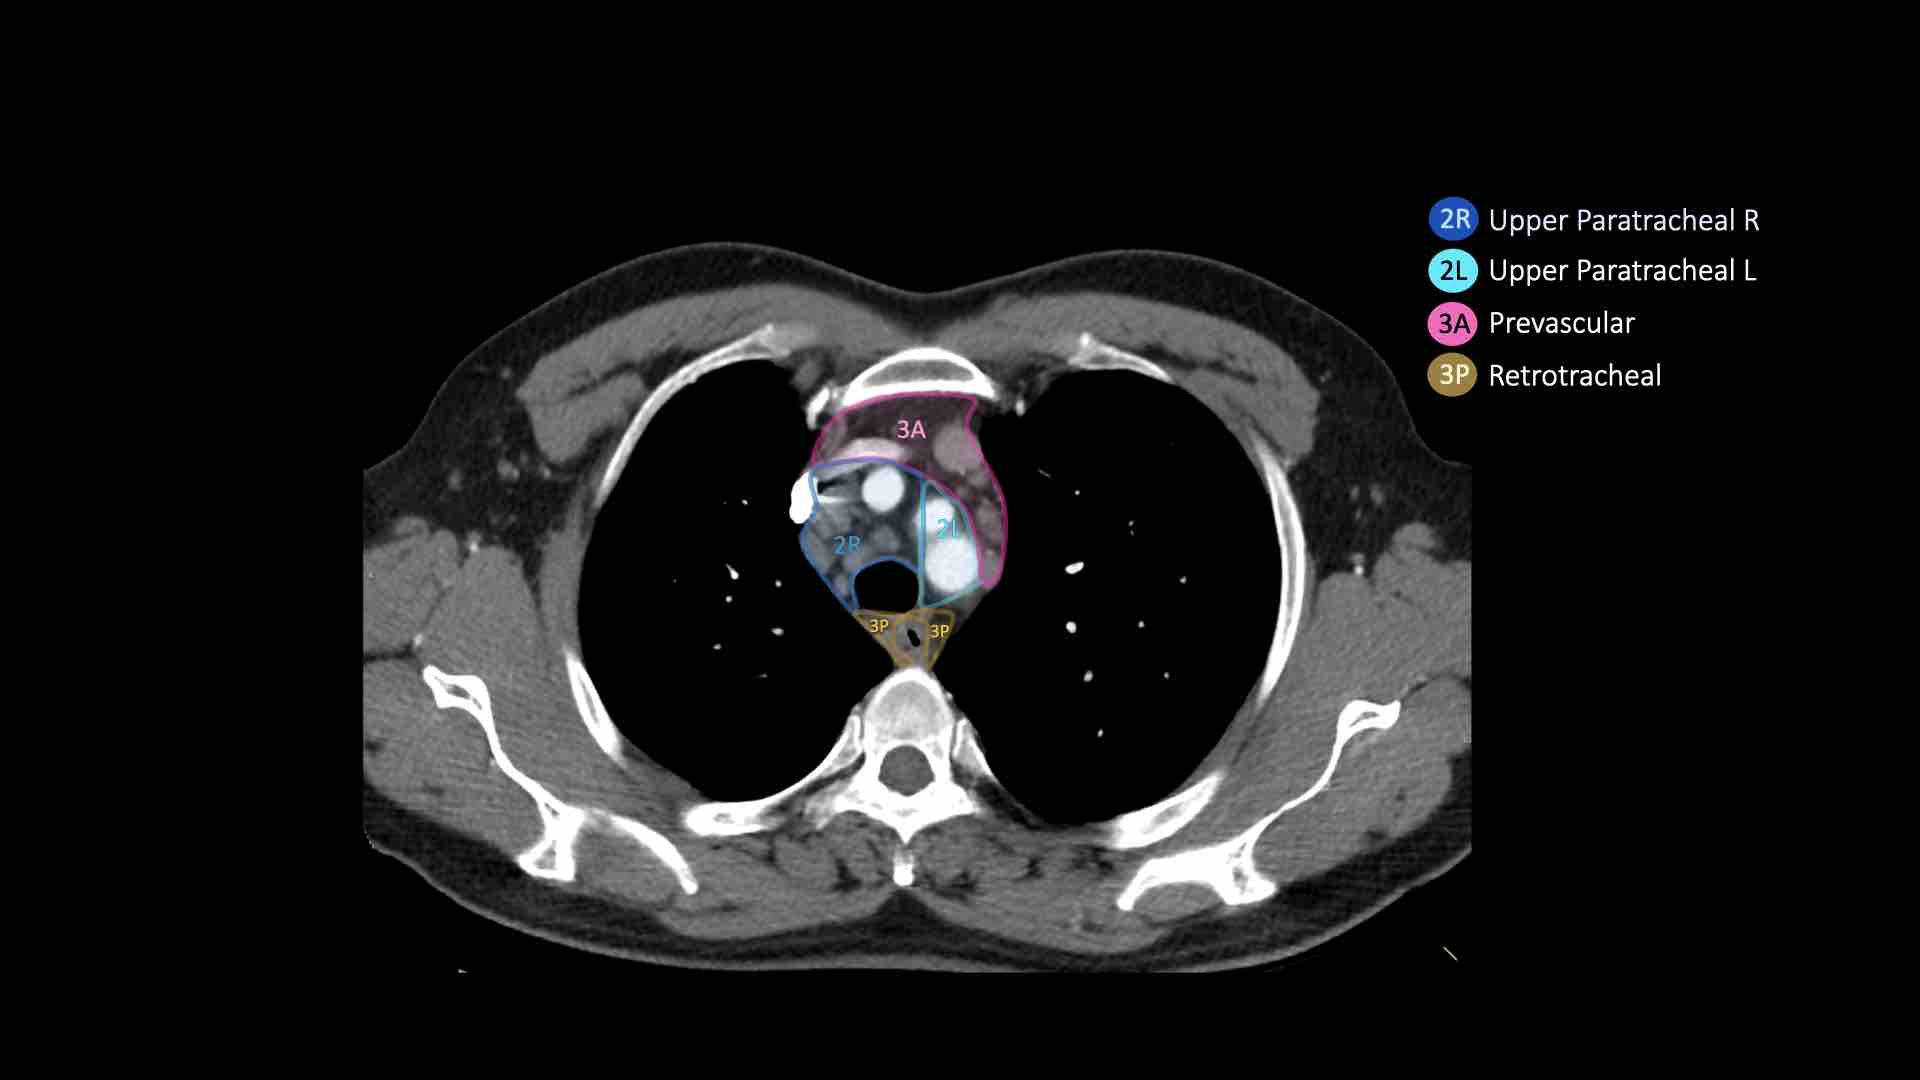

2R.Cạnh khí quản trên

Hạch nhóm 2R trải dài đến bờ bên trái của khí quản.

Từ bờ trên của cán ức đến điểm giao nhau giữa bờ dưới tĩnh mạch vô danh (tĩnh mạch tay đầu trái) với khí quản.

2L.Cạnh khí quản trên

Từ bờ trên của cán ức đến bờ trên của quai động mạch chủ.

Hạch nhóm 2L nằm ở phía trái của bờ bên trái khí quản.

3A.Trước mạch máu

Các hạch này không tiếp giáp với khí quản như các hạch ở nhóm 2, mà nằm ở phía trước các mạch máu.

3P.Trước cột sống

Các hạch không tiếp giáp với khí quản như các hạch ở nhóm 2, mà nằm sau thực quản, tức là ở vị trí trước cột sống.

2R. Hạch cạnh khí quản trên bên phải

Ranh giới trên: bờ trên cán ức.

Ranh giới dưới: giao điểm của bờ dưới tĩnh mạch vô danh (tĩnh mạch tay đầu trái) với khí quản.

2L. Hạch cạnh khí quản trên bên trái

Ranh giới dưới: bờ trên quai động mạch chủ.

Bên trái là hạch nhóm 2 nằm phía trước khí quản, tức là hạch 2R.

Ngoài ra còn có một hạch trước mạch máu nhỏ, tức là hạch nhóm 3A.

3. Hạch trước mạch máu và trước cột sống

Hạch nhóm 3 không nằm kề khí quản như hạch nhóm 2.

Chúng có thể là:

3A nằm phía trước các mạch máu, hoặc

3B nằm phía sau thực quản, vốn nằm ở vị trí trước cột sống.

- Cạnh khí quản trên: phía dưới xương đòn, bên phải nằm trên giao điểm của bờ dưới tĩnh mạch vô danh (tĩnh mạch tay đầu trái) với khí quản, bên trái nằm trên cung động mạch chủ

- Trước mạch máu và Sau khí quản: nằm trước các mạch máu (3A) hoặc trước cột sống (3P)